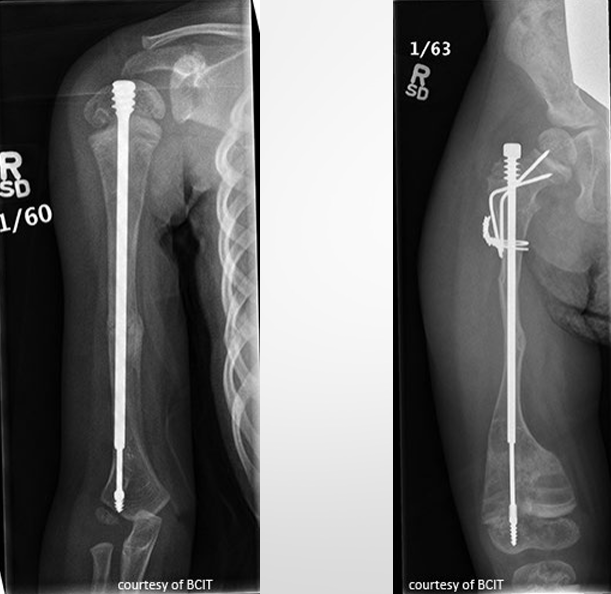

Treatment - Osteogenesis Imperfecta

focus is to prevent fx → extendable rods in long bones

medications to reg. osteoclast formation